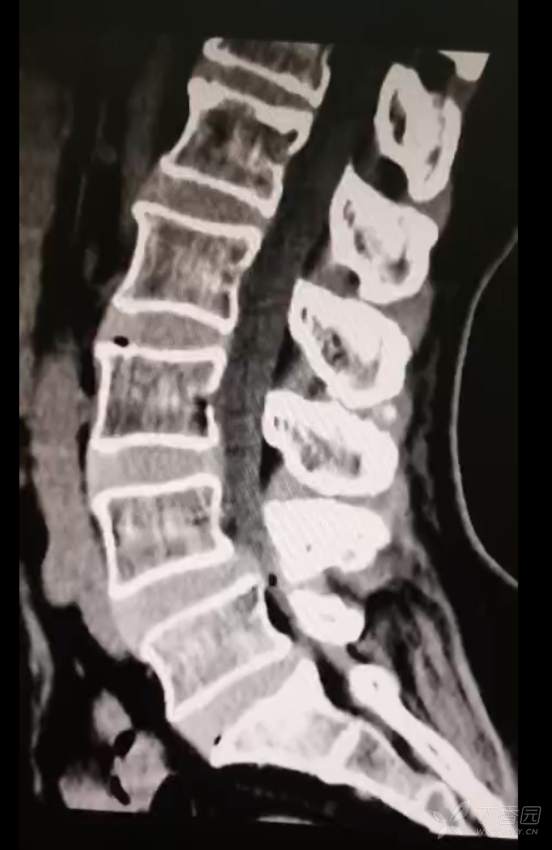

黄骨头脊柱内镜——腰4-5椎管狭窄侧路减压一例